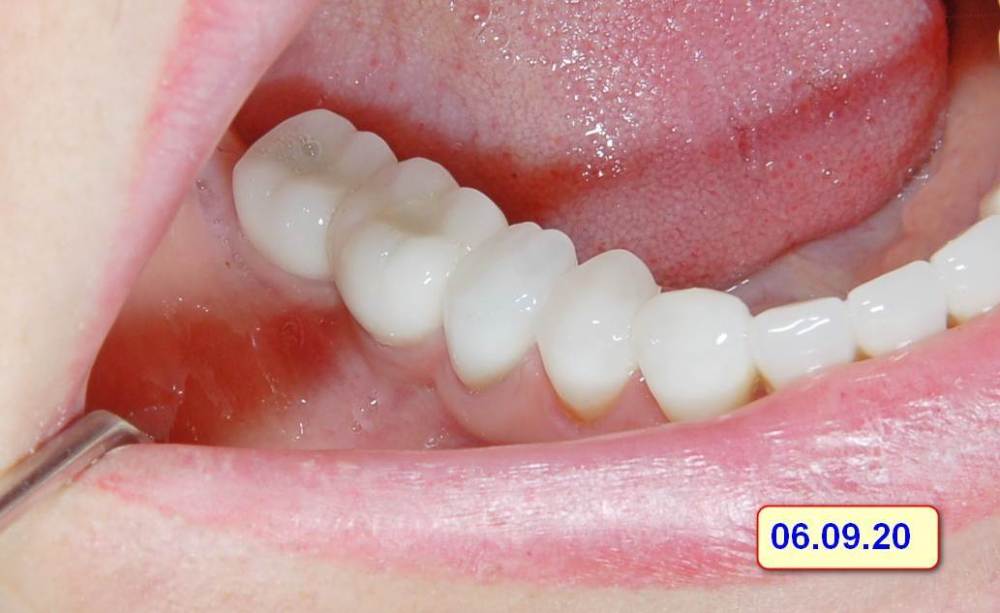

Большой Зеленый Опубликовано 15 августа, 2023 Поделиться Опубликовано 15 августа, 2023 Винтовая фиксация . 8 лет наблюдений .Полет нормальный. Немного прокрасились пломбы в шахтах. Пациентка довольна и счастлива. Привела уже вагон беззубых друзей и родственников. P/S. Система имплантов Ирис...:) 1 Ссылка на комментарий